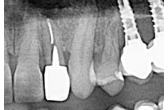

Colocación de implantes en 34 y 36 con ROG simultánea